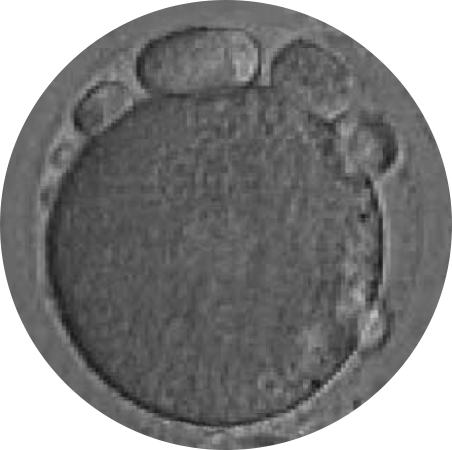

ÓVULO RESTAURADO

ÓVULO CON BAJA CALIDAD OVOCITARIA